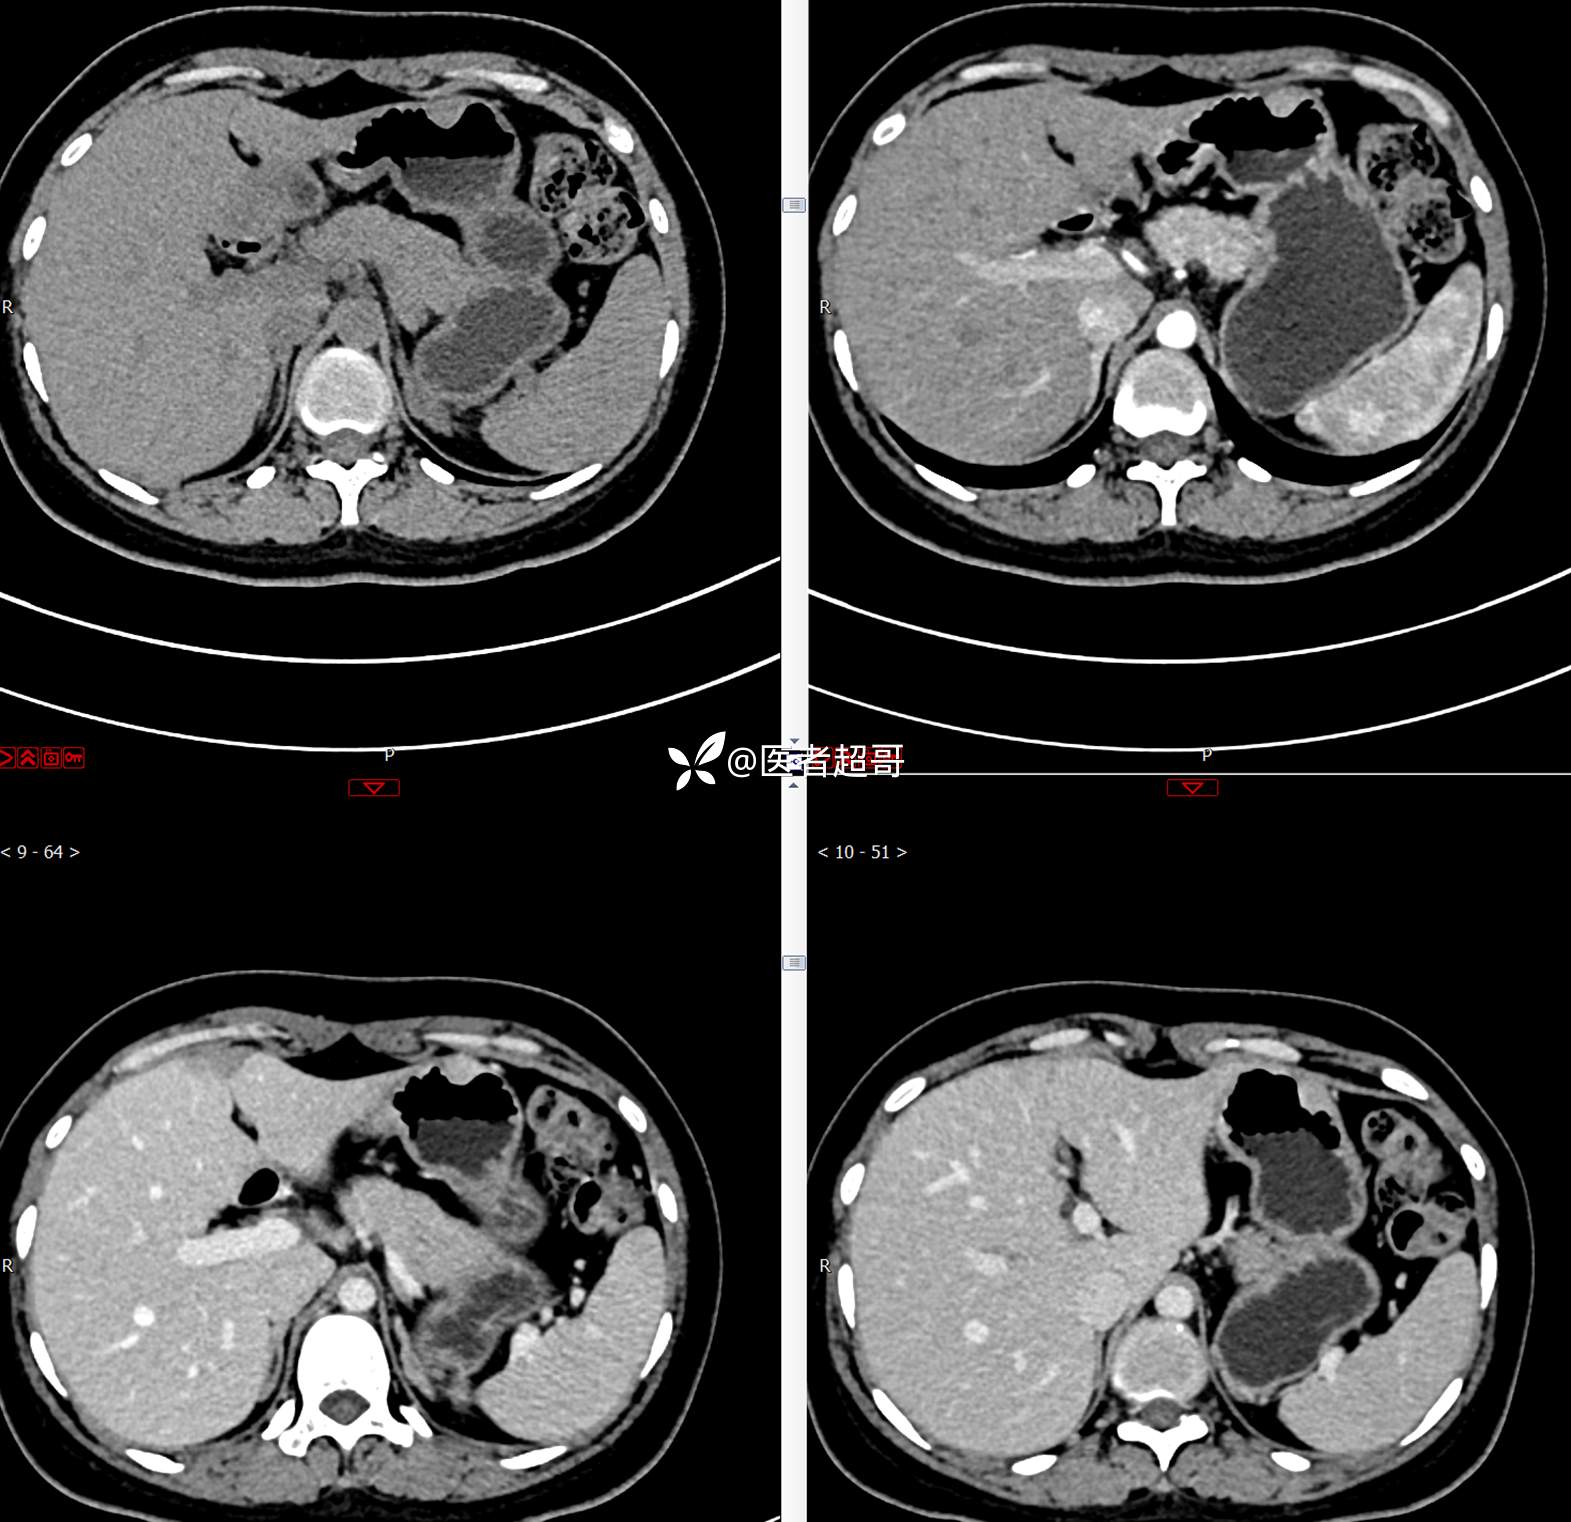

青年男性,恶心、呕吐5年,发现胃肿物3月,有结果,请分析!

主 诉:恶心、呕吐5年,发现胃肿物3月。

现病史:患者5年前无明显原因及诱因出现恶心、呕吐,多于进食后出现,呕吐物为胃内容物,无鲜血及咖啡样物质,偶有空腹痛,无放射痛,无腹泻,无便秘,无黑便、鲜血便,无胸闷、心慌,无头痛、头晕,曾就诊于当地医院口服“消炎药”治疗(具体不详),上述症状反复出现,3月余前就诊于市第二人民医院,行胃肠镜检查:慢性浅表性胃炎、胃体粘膜下占位,后就诊于我院超声内镜检查:胃体肿物,似来源于黏膜下层,今为行进一步治疗来我科就诊,门诊以“胃肿物”收住入院。患者自发病以来,神志清,精神可,饮食一般,睡眠可,大小便正常,体重无明显变化。